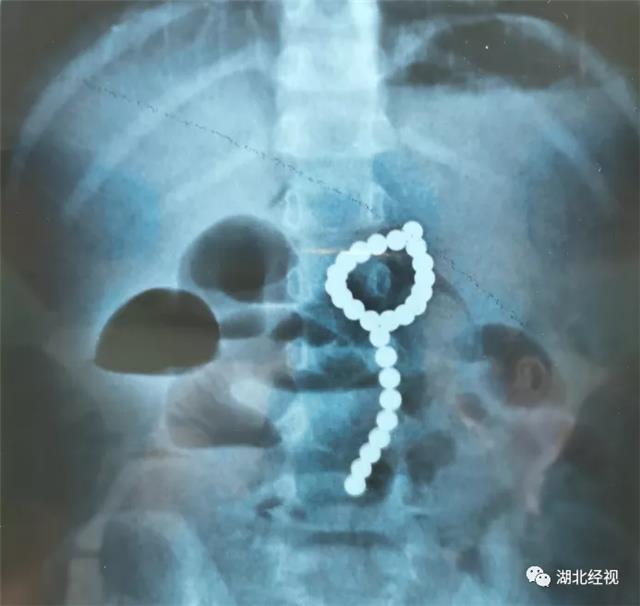

拍片发现,莎莎腹部有异常高密度阴影,看形状像是一颗一颗的小珠子,一数有26颗。

在父母的追问下,莎莎才说她吞了“彩色的小珠珠”,推测应该是家里的玩具磁力珠。当地医生建议立即转院,12日清晨,莎莎一家到达武汉儿童医院。

经过紧急术前检查,早上8点,医生给莎莎做了全麻下胃镜检查术。术中,医生发现莎莎胃里有大量成串的磁力珠,部分堆积在胃幽门口,成串的“骑跨”在胃角上。

医生拨动磁力珠发现,有一颗磁力珠深陷在胃壁中,考虑穿孔可能很大,经讨论后,决定直接转外科手术。

紧急与家长沟通并取得其同意后,医生对莎莎进行剖腹探查,结果在莎莎胃内探查到大量的磁力珠,在胃大弯、小弯处发现穿孔,证实了之前的推测。医生在胃内共找到26颗磁力珠并顺利取出。